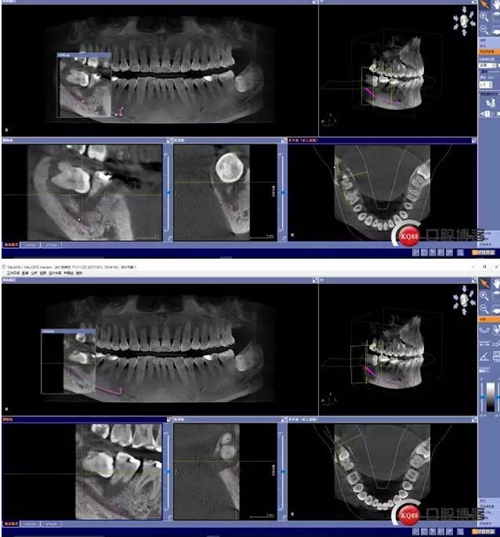

X線及CBCT檢查:47、48根尖周區(qū)大面積低密度影像,波及下牙槽神經(jīng)管,部分區(qū)域至神經(jīng)管以下。CBCT顯示神經(jīng)管走形于47根尖炎癥區(qū)下方(已侵犯)48炎癥區(qū)頰側(cè)(已侵犯)

術(shù)前CBCT分析

術(shù)后影像分析

對于曲面斷層片的分析,當(dāng)智齒埋伏牙的根尖與下牙槽神經(jīng)有重疊影像時(shí),常常可采用觀察重疊部分牙根的牙周膜和硬骨板是否連續(xù),下頜管是否比牙根密度高,下頜管是否變窄等,來辨別牙根與神經(jīng)管的位置關(guān)系。當(dāng)然曲面斷層片也很難避免其失真變形的自身局限性。拍攝CBCT能更為直觀預(yù)估其風(fēng)險(xiǎn)。但切記盲目的嘗試和挑戰(zhàn)。